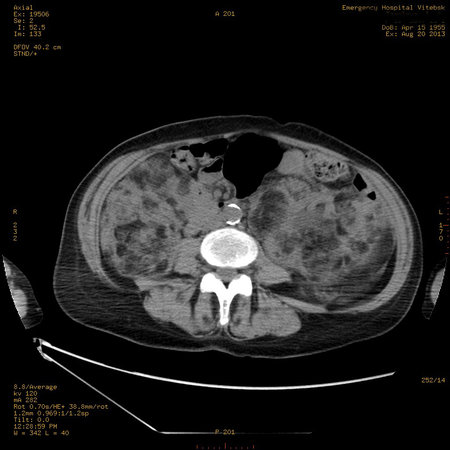

УЗИ почек - туберозный склероз

Пожилая женщина с нормальными мочевиной и креатинином.

Ангиомиолипоматоз почек , думаю компонент туберозного склероза.

Да, туберозный склероз.

Случай консультирован на кафедре радиологии Католического университета г.Лёвен (Бельгия) - зав каф. профессор Р.Оуен.